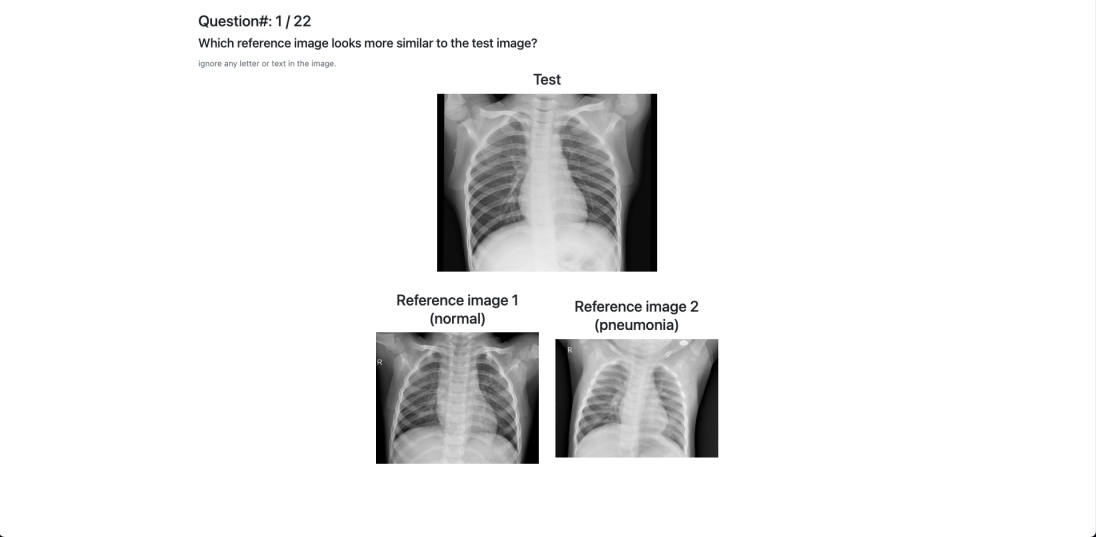

5.1 Triplet annotation

We recruit crowdworkers on Prolific to acquire visual similarity triplets. In each question, we show a reference image on top and two candidate images below, and ask a 2-Alternative-Forced-Choice (2AFC) question: which candidate image looks more similar to the reference image? A screenshot of the interface can be found in the appendix. To generate triplets for annotation, we first sample the reference image from either the training, the validation, or the test set. Then for each reference image, we sample two candidates from the training set. We sample the candidates only from the training set because in decision support, the selected examples should always come from the training set, and thus we only need to validate and test triplet accuracies with candidates from the training set.

For BM we recruit 80 crowdworkers, each completing 50 questions, giving us 4000 triplets. For CXR we recruit 100 crowdworkers, each answering 20 questions, yielding 2000 triplets. Our pilot study suggests that visual similarity judgment on chest X-rays is a more mentally demanding task, so we decrease the number of questions for each CXR survey.